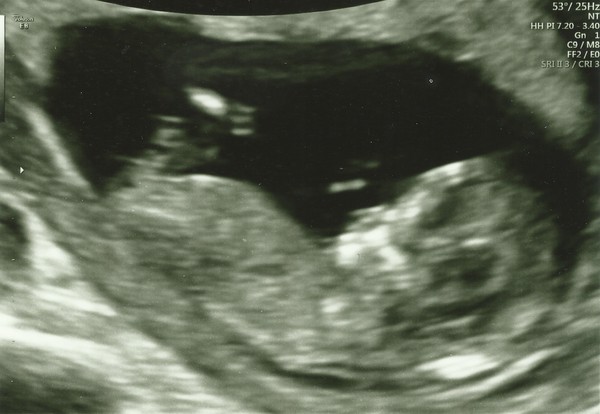

Chembecky · 19/06/2019 19:36

@NoMoreFastCars82 sorry for your loss. I went for my 12 week scan today and I was so nervous. My baby is healthy and the correct size - although it was a bit difficult to measure as it was hanging out upside down! And I was too-ing and fro-ing to the loo - I was told to do a half wee?!?! Here is a blurry pic :)

@Chembecky this is what I meant ☺️ huge congrats!!! and I am over the moon for you!!! Lol at half wee, bloody hard that when you're in full flow lol xx

DaisyMay25 · 19/06/2019 19:43

@Chembecky beautiful scan! Glad all went well. I love the half wee, like I'll know when my bladder is half empty...

It was a trainee who told me to do it. Then the other sonographer was like "blimey your bladder filled up quickly" and I had to awkwardly say I was told to do a half wee....